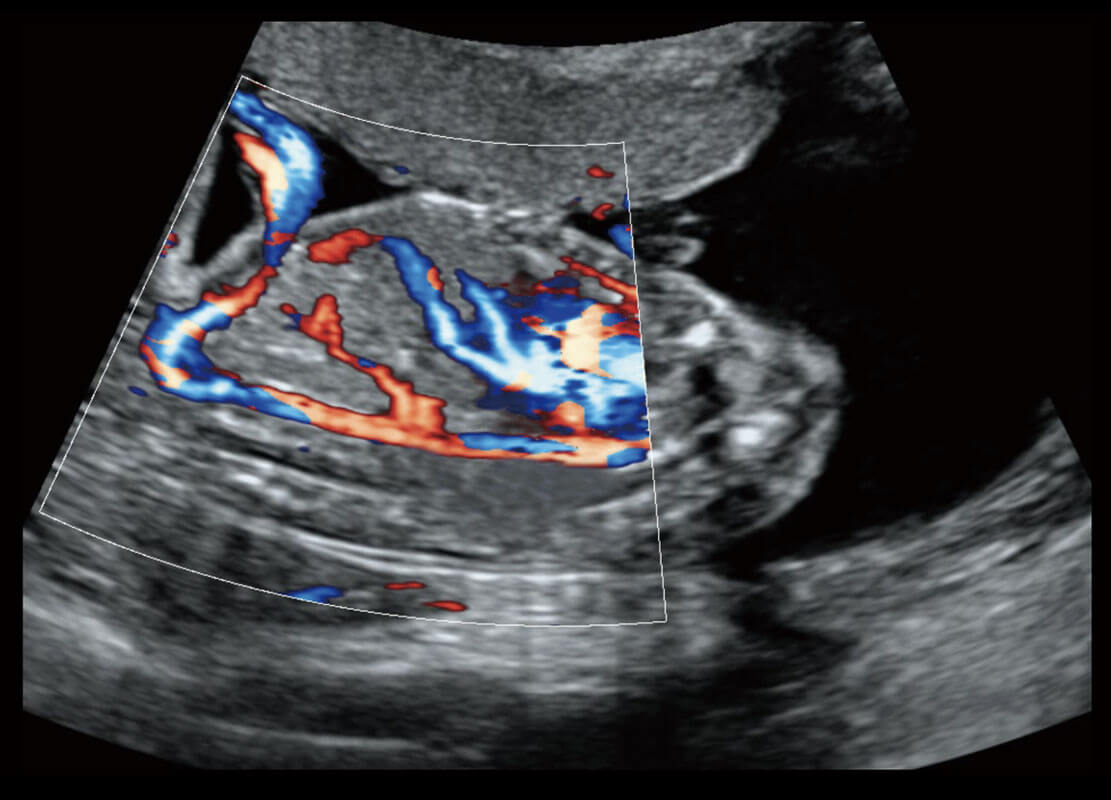

乳腺超声 / 新生儿

P60搭载宽频带线阵探头、宽景成像、弹性成像技术,为您提供乳腺应用方案。P60支持高频相控阵探头、线阵探头、腹部高频探头、腹部微凸探头等,丰富的探头群搭载敏感的彩色血流成像,适用于新生儿多种脏器检测要求,满足新生儿筛查需求。

• 新生儿肝血管癌

• 新生儿心脏